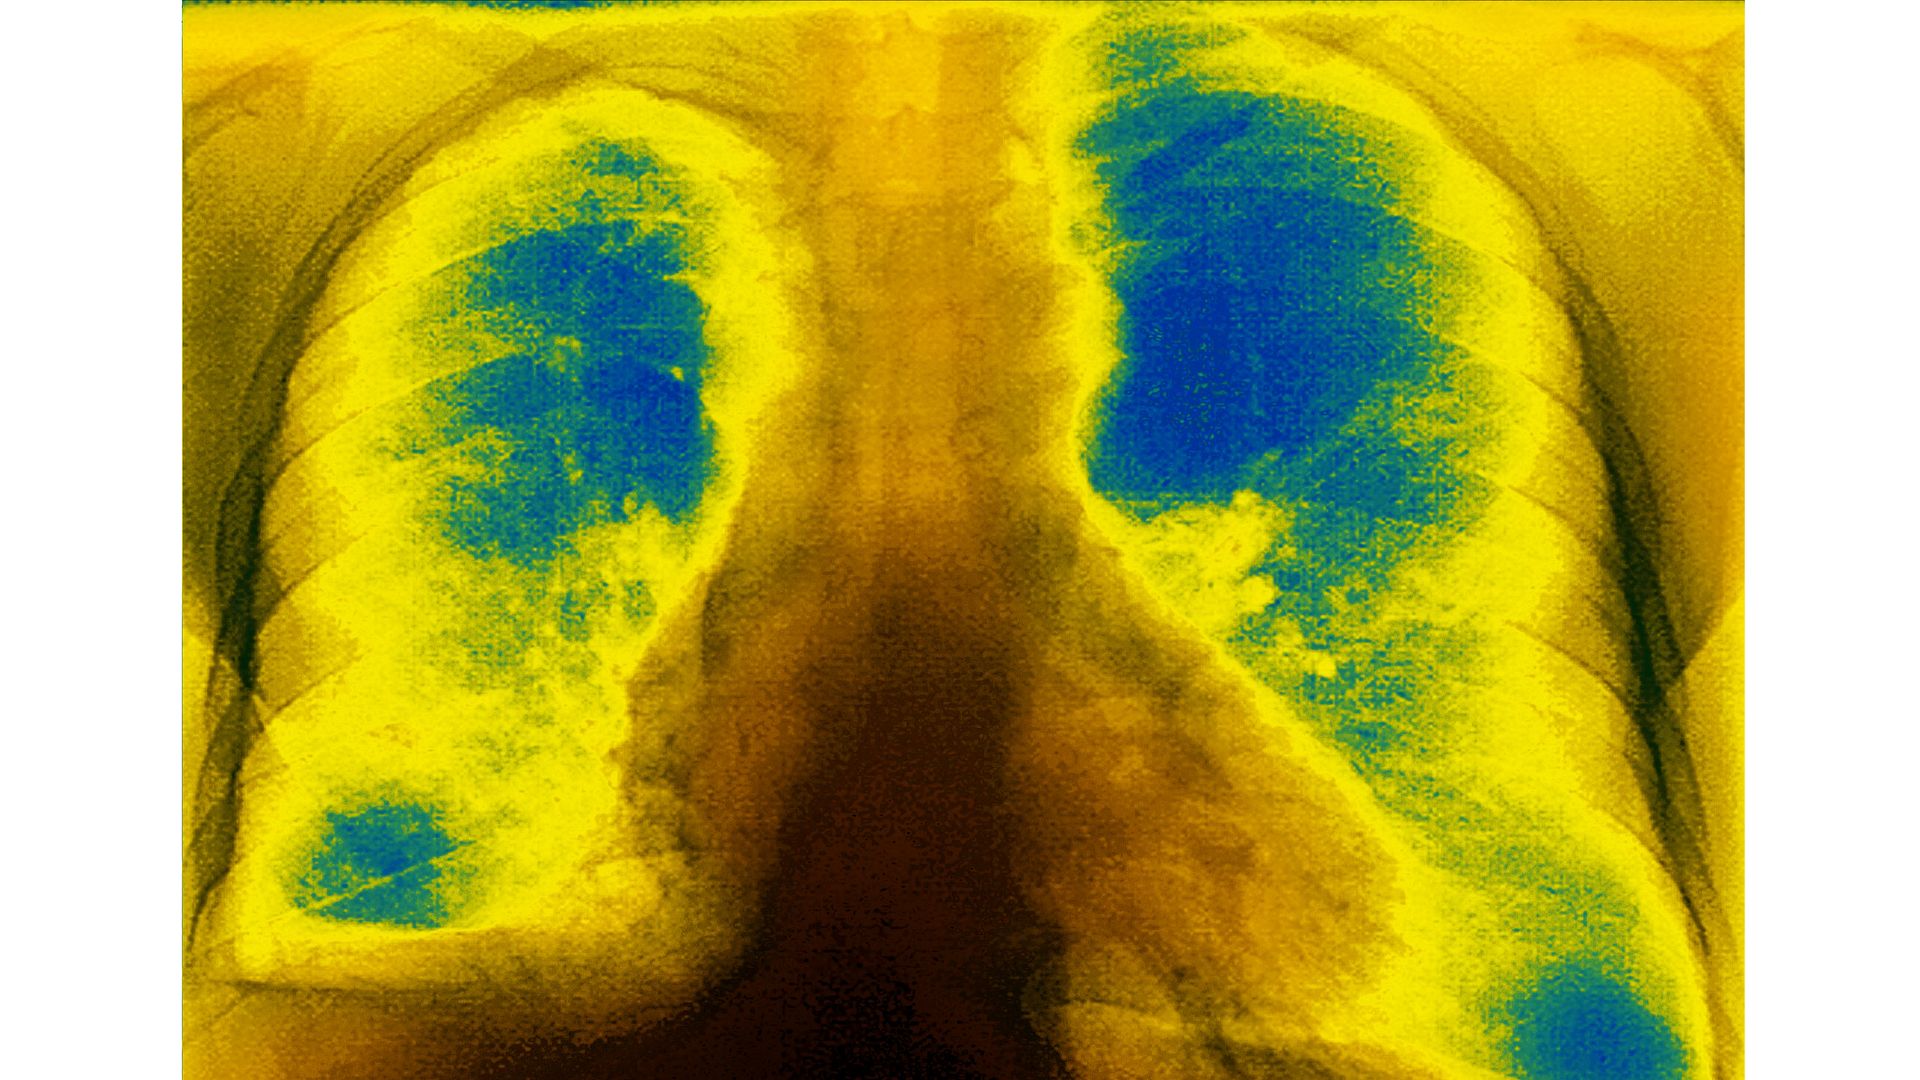

Mucoviscidosis (accumulation of mucus in the respiratory tract), seen on a frontal X-ray of the chest. Photo: BSIP/Universal Images Group via Getty Images